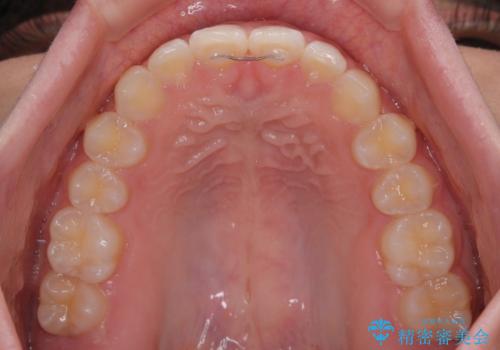

- 前歯の隙間を気にして来院された患者様です。

口元の突出感があり、小臼歯4本を抜歯して口元を引っ込める矯正治療も提案しましたが、本人は口元の突出感は気になっていないとのことで、インビザラインにて隙間やデコボコを改善することとしました。

軽度の歯列不正であったため、廉価版のインビザライン・モデレートパッケージにて治療を終えることができました。